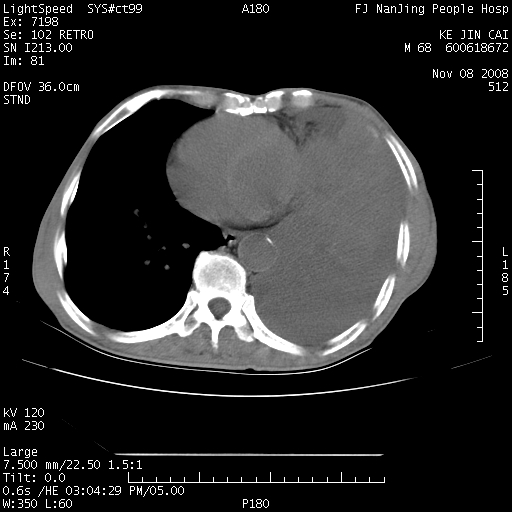

是个很有看头的病例,咋人气那么不旺?没多少人兴趣呢?这个病例几大怪:1   恶性肿瘤侵犯心肌左房怪,心肌一般不会被恶性肿瘤侵犯吧?2   左下肺均匀实变怪,内无含气,有别一般不张实变,含气肺泡完全为液体取代,而非一般不张实变的肺萎陷,冷不丁还以为是肿大的脾脏3   肿瘤本身怪,像tb肺不张4   这么有看头的病例没人气怪。呵呵。

左肺恶性肿瘤侵犯肺动脉,左心房内瘤栓,胸膜转移。